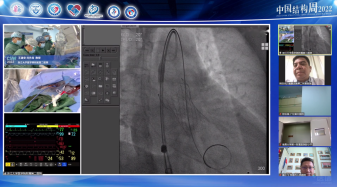

广东省人民医院罗建方教授团队带来一例二尖瓣机械瓣置换术后TAVR手术。由于该患者也存在三尖瓣关闭不全问题,但考虑到右心衰不严重,则优先处理主动脉狭窄问题。术后患者血流动力学稳定,舒张压64mmHg,无瓣周瘘问题。

手术策略:全身麻醉、右股入路、无预扩张、23mm或26mm可回收输送系统。